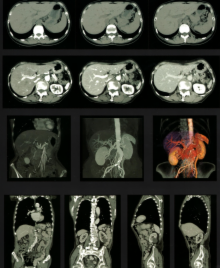

胸・腹部

単純CTおよび造影CT

3DCTおよび3DCTA

体幹 T1画像、T2画像

T2*画像

脂肪抑制画像

造影MRI

MRCP